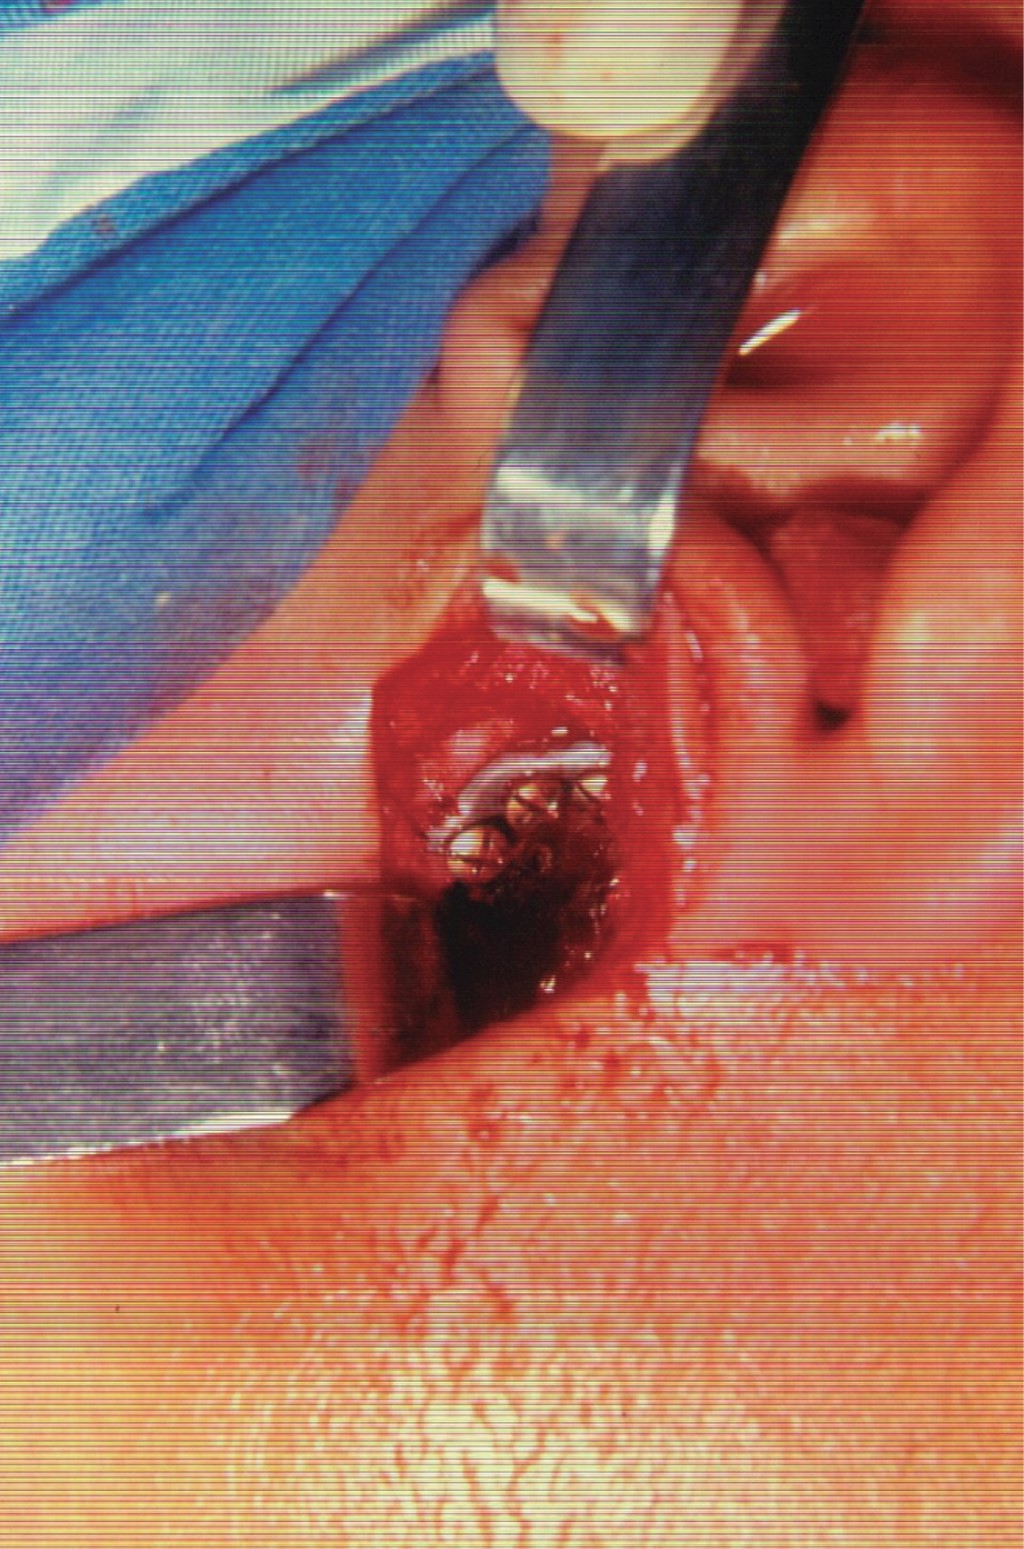

Se trata de paciente masculino de siete años de edad atendido en la Unidad Médica de Alta Especialidad (UMAE) No. 71 del Instituto Mexicano del Seguro Social, en la ciudad de Torreón, Coahuila, México. Acude por presentar imposibilidad de la apertura bucal desde la edad de cinco años, teniendo como único antecedente de importancia traumatismo facial al estar jugando y caer de su propia altura, evolucionando con progresiva limitación de apertura bucal hasta no poder abrirla en lo absoluto. A la exploración física, nula apertura bucal, aspecto facial con mínima alteración estética, micrognatia mandibular sin impacto estético importante (Figura 1). La radiografía inicial muestra anquilosis temporomandibular bilateral (Figura 2). Bajo anestesia general, intubación nasal con fibroscopio, se realiza liberación bilateral de anquilosis temporomandibular eliminando fragmentos óseos anquilosados y colocando prótesis metálicas de cavidad glenoidea de aleación cromo, cobalto, molibdeno (Figura 3), logrando adecuada apertura bucal sin complicaciones qué comentar (Figura 4). A la edad de 11 años se colocan prótesis metálicas de cóndilo de manera bilateral del mismo metal y mentoplastia de avance. Radiografía del paciente a la edad de 23 años (Figura 5).

Figura 3